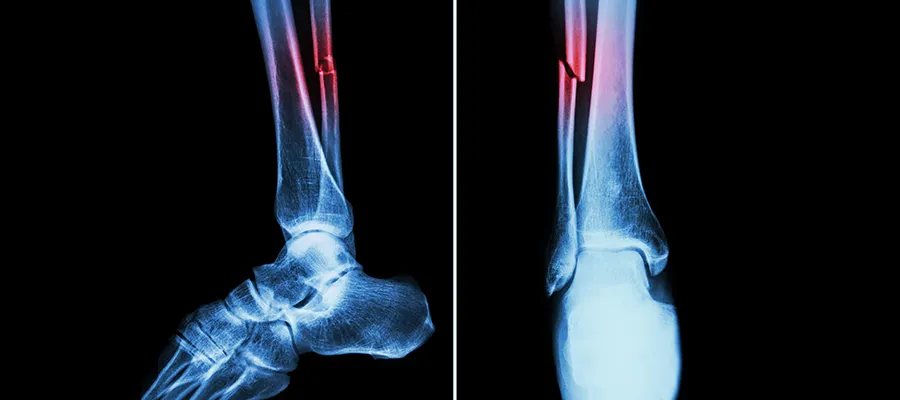

fractured bone

Osteogenesis Imperfecta is caused by genetic mutations that lead to abnormalities in an important component of bone called collagen.

People with the disease have extremely fragile bones that break easily, often from mild trauma or for no apparent cause.